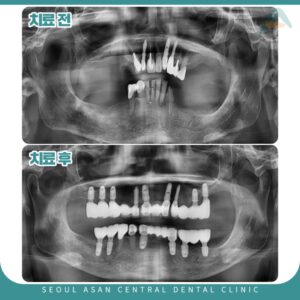

성남치과 체계적인 전체임플란트 식립을 안녕하세요. 성남치과 서울아산센트럴입니다. 충치나 치주 질환, 예기치 못한 사고 등에 의해서 치아를 상실하게 되는 경우가 있는데요. 상실된 치아를 수복하는 방법으로는 요즘 대중화되어있는 임플란트를 가장…